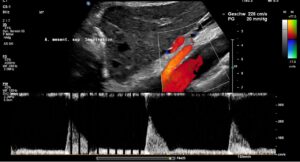

As a result of the pronounced lordosis and the associated ventral displacement of the aorta, the left renal vein is also severely compressed.

The narrowest point is located at the arcuate origin of the right renal artery. The lumen of the renal vein is barely recognizable. As a result, there is a significant acceleration of flow from 14 cm/s to the left of the aorta to 235 cm/s at the narrow point. This is a severe hemodynamically significant outflow obstruction of the left kidney, often somewhat misleadingly referred to as nutcracker syndrome. This constellation is responsible for the pain radiating from the epigastrium to the left hypochondrium. As the stomach fills, the compression exerted by the greater curvature on the tense renal vein intensifies the discomfort in the epigastrium. The left renal vein runs relatively far cranially.

A collateral circulation branches off from the left renal vein to the spinal canal—a so-called tronc réno-rachidièn—which feeds 148 ml/min into the epidural plexus in a horizontal body position. When standing, the perfusion of the vessel increases to 531 ml/min.

This contributes to an increase in pressure in the spinal canal and subsequently intracranially, which would explain headaches and, in some cases, neurological deficits in the cranial nerves (visual disturbances, speech disorders, bulbar motility disorder). The drastic increase in spinal and thus cerebral congestion when standing after eating. This corresponds exactly with the patient’s description of unbearable headaches after every meal.